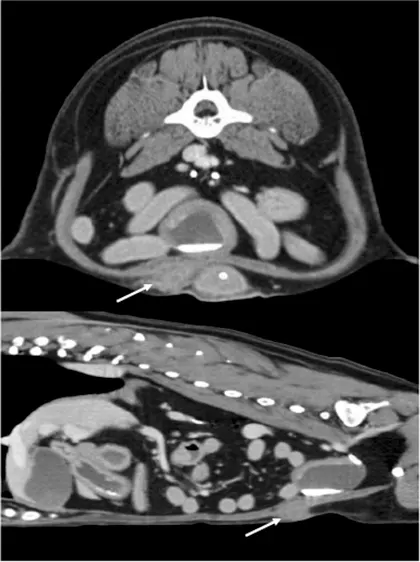

Figure 1 Contrast CT scan (axial and sagittal) showing needle-tract metastasis (arrows) in the abdominal body wall of a dog resulting from a needle aspirate of a primary bladder transitional cell carcinoma.

Two important points are illustrated and discussed in the context of this case report involving a dog with bicavitary effusion that underwent thoracocentesis for cytologic assessment. First, thoracocentesis is generally held to be a relatively simple, routine procedure associated with low procedural morbidity. In the case reported, a presumed needle tract metastasis resulted. Importantly, the authors referenced data in the human literature that suggest needle-tract metastasis is a rare event and that diagnostic information gained outweighs this uncommon risk.1

For diffuse malignant disease for which local curative therapies are not possible (eg, carcinomatosis), needle-tract metastasis is not likely to impact prognosis or treatment; therefore, overall risk is even lower. In contrast, when dealing with potentially localized tumors (eg, solitary primary lung tumors, localized transitional cell carcinoma of the bladder), the clinical consequences of needle-tract metastasis may be greater as therapeutic interventions directed at local control of disease (eg, surgery, radiation therapy) may exist. In those instances, although risk is low, it must be weighed against the likelihood of curative or durably controllable local disease management and discussed in context with the client.